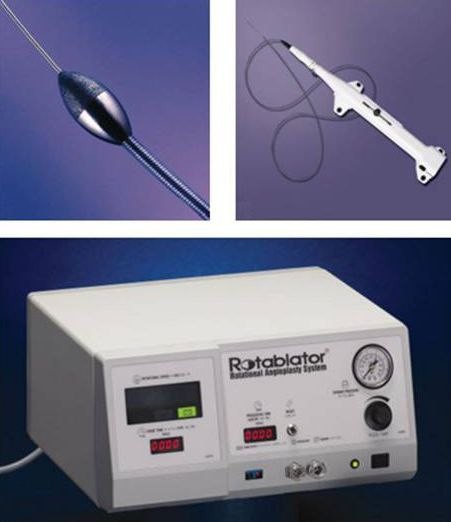

冠状动脉旋磨术器械

项目类型

体验医疗区2

起投金额

600USDT

每日释放:0.55

释放周期:10 天

已购: 40000

剩余: 0